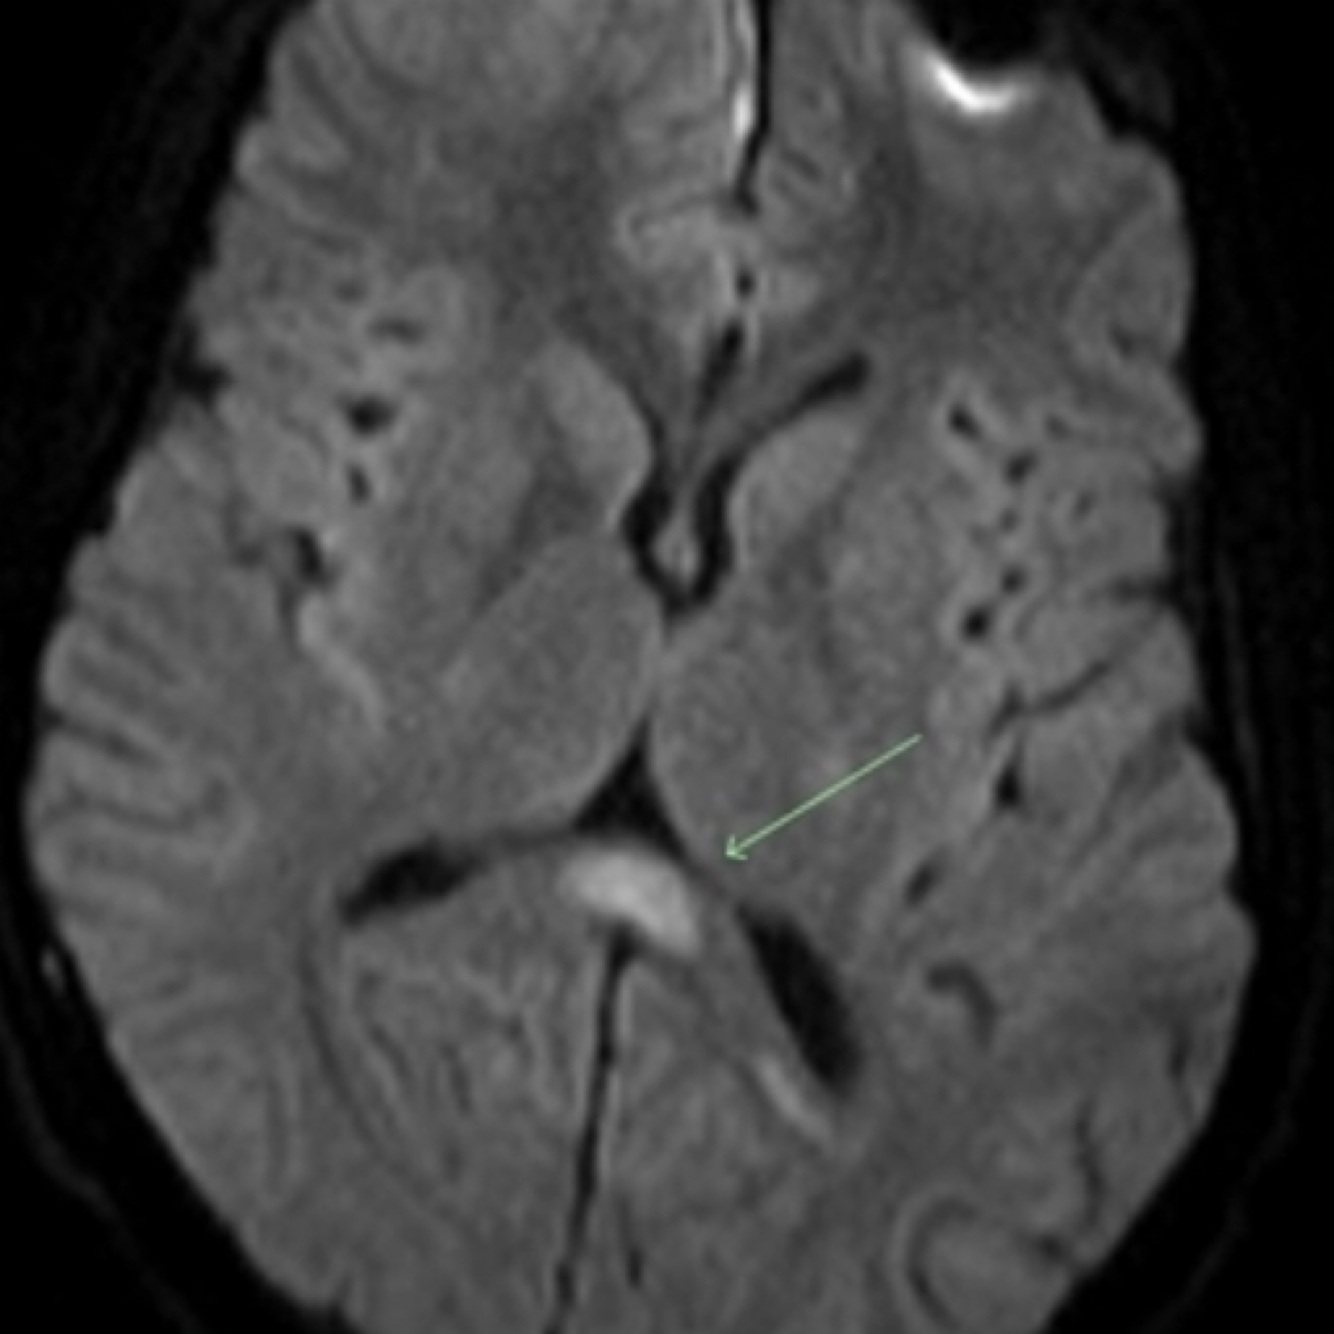

What sign is this image depicting

Boomerang sign is a boomerang-shaped region of cytotoxic edema in the splenium of the corpus callosum typically seen in cytotoxic lesions of the corpus callosum (CLOCCs)